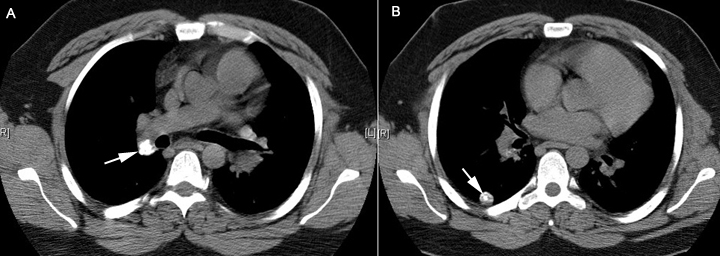

Solitary pulmonary nodule / GranulomaA. Calcified hilar node Note that a lesion which has been stable in size for two years and/or with demonstrable calcium are two strong points in favor of a benign lesion. |